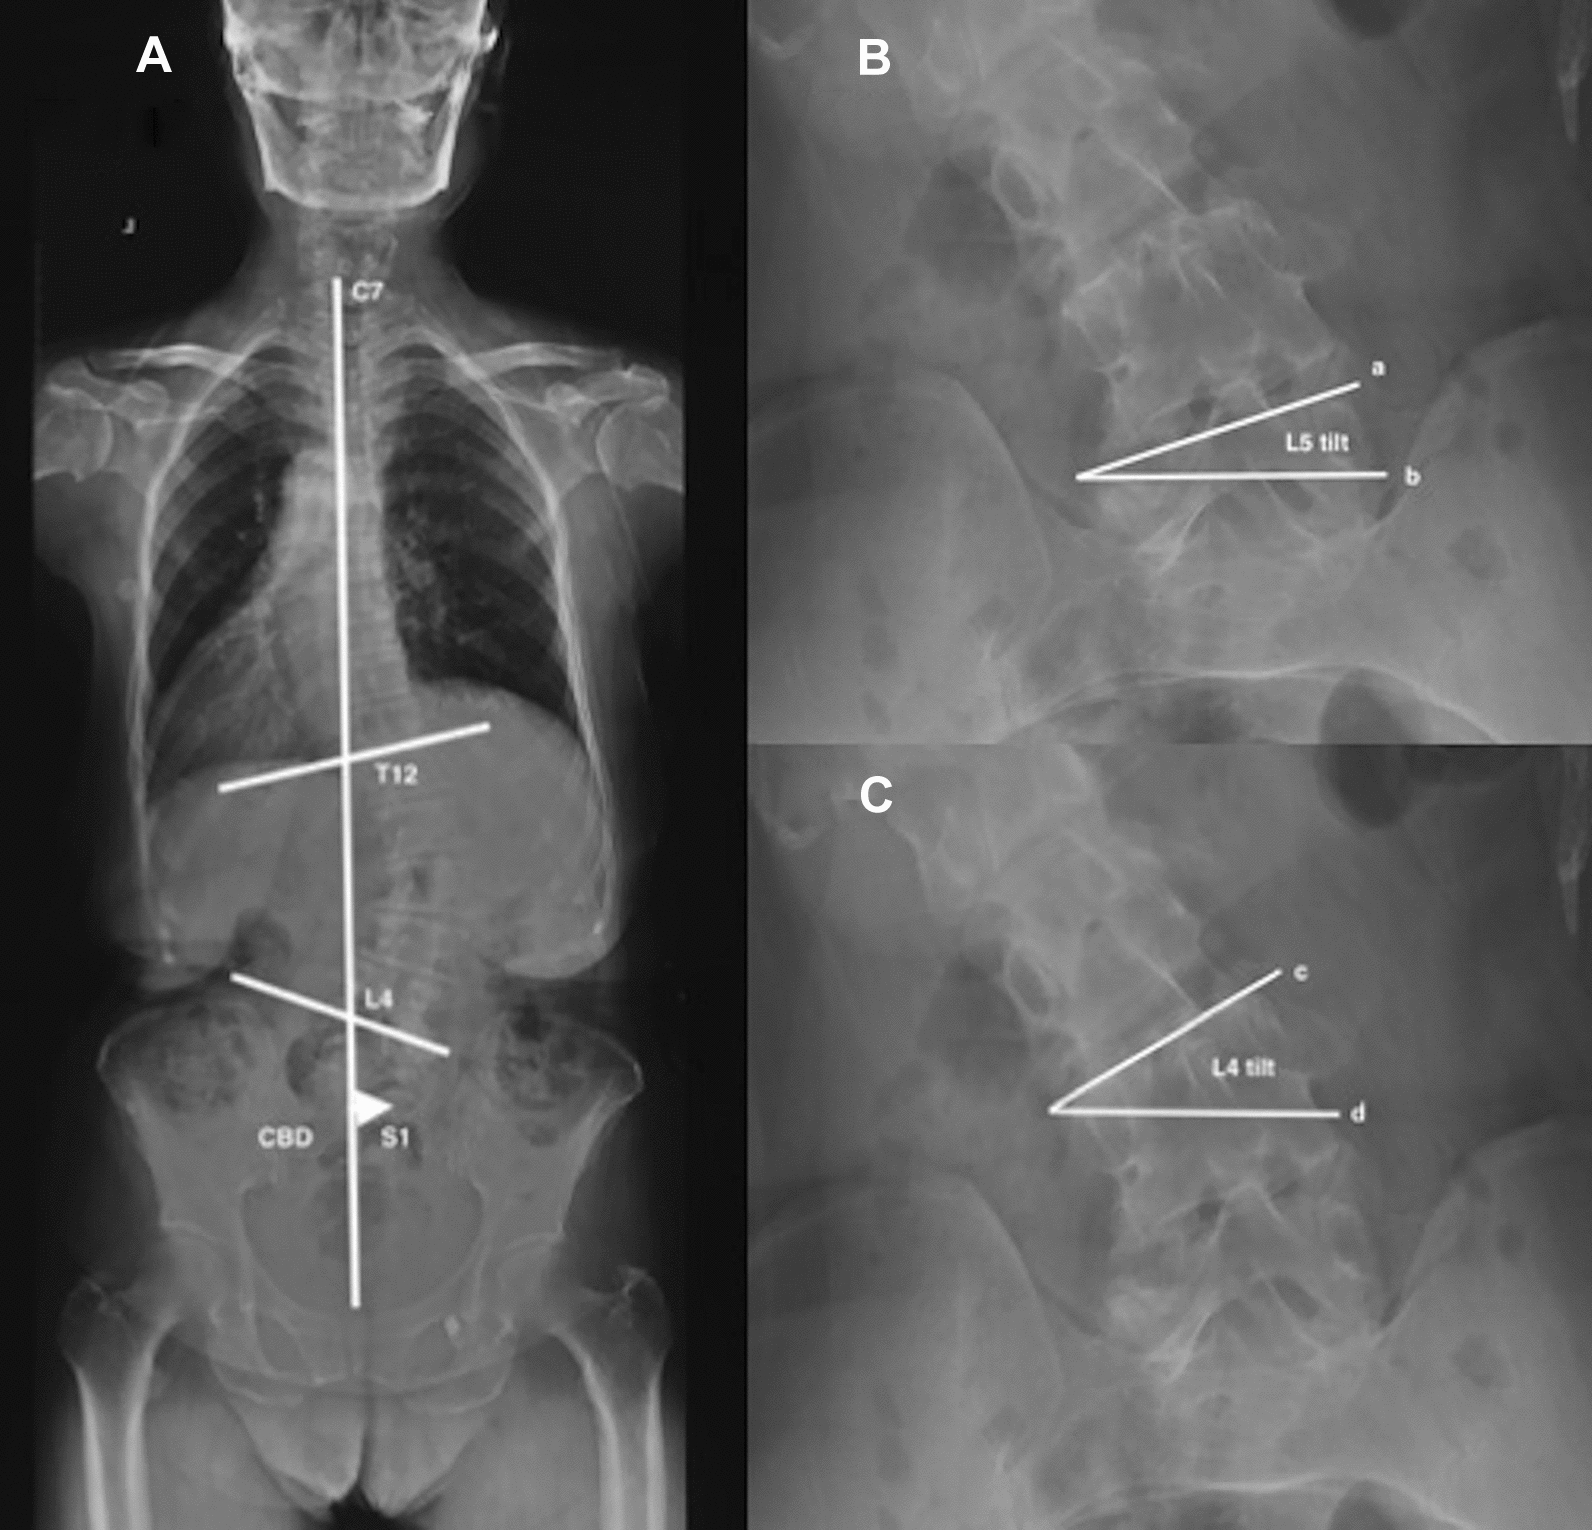

4 coronal parameters were recorded as follows:

- Major Cobb (MC), the Cobb angle between the superior endplate of the most tilted vertebra cranially and the inferior endplate of the most tilted vertebra caudally (left scoliosis was recorded as negative [−], right scoliosis as positive [+]).

- Coronal balance distance (CBD), the horizontal distance between the middle of S1 and the C7 plumb line (C7PL). If the C7PL locating at the left of S1, CBD was recorded as the negative value (−), or else, as the positive value (+).

- L4 coronal tilt, the angle between superior endplate of L4 and the horizontal line (left side was recorded as the negative value [−], and right side as the positive value [+]).

- L5 coronal tilt, the angle between superior endplate of L5 and the horizontal line (left side was recorded as the negative value [−], and right side as the positive value [+]). Figure 1A–C